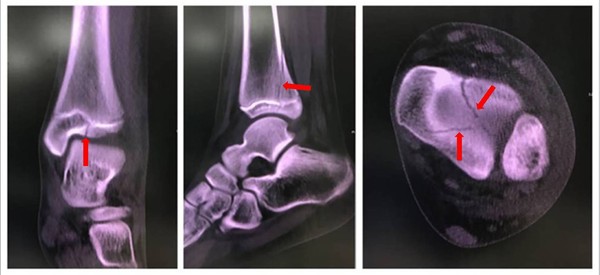

▲踝關節遠端脛骨三平面型骨折透過電腦斷層能夠較清楚看出來。(圖/嘉義長庚醫院提供)

沈世勛解釋,張小妹妹這樣的骨折其實是很容易被忽略,在一般的X光上並不明顯,但在腳踝的電腦斷層上卻可以清楚看到複雜的骨折情形,這種情況稱之為踝關節遠端脛骨三平面型骨折。他表示,這類型骨折在青少年踝關節骨折中約佔5-15%,依文獻統計其發生率約為7-21%,是青少年腳踝受傷時需要特別注意的一種骨折。